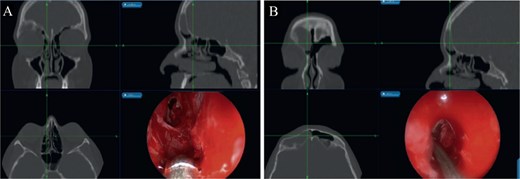

The patient underwent image-guided ESS with frontal sinusotomy. A 45-angled endoscope helped in recognition of the mucocele, which was treated with marsupialization (Fig. 5). The thick anterior inferior wall was removed. During 2 years of follow-up, no recurrence or complication was observed.

(A) Mucocele Draf IIa wide frontal sinusotomy, (B) image-guided wide marsupialization of mucocele.